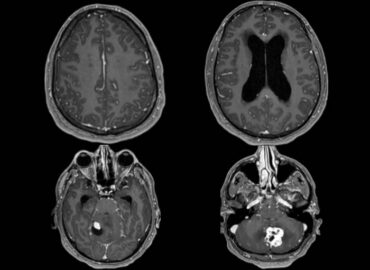

Sexo femenino de 35 años APP Ca de cuello

Paciente que consulta por cefalea occipital, de 12 hs de evolución, acompañado de vómitos alimenticios, fotofobia y fiebre